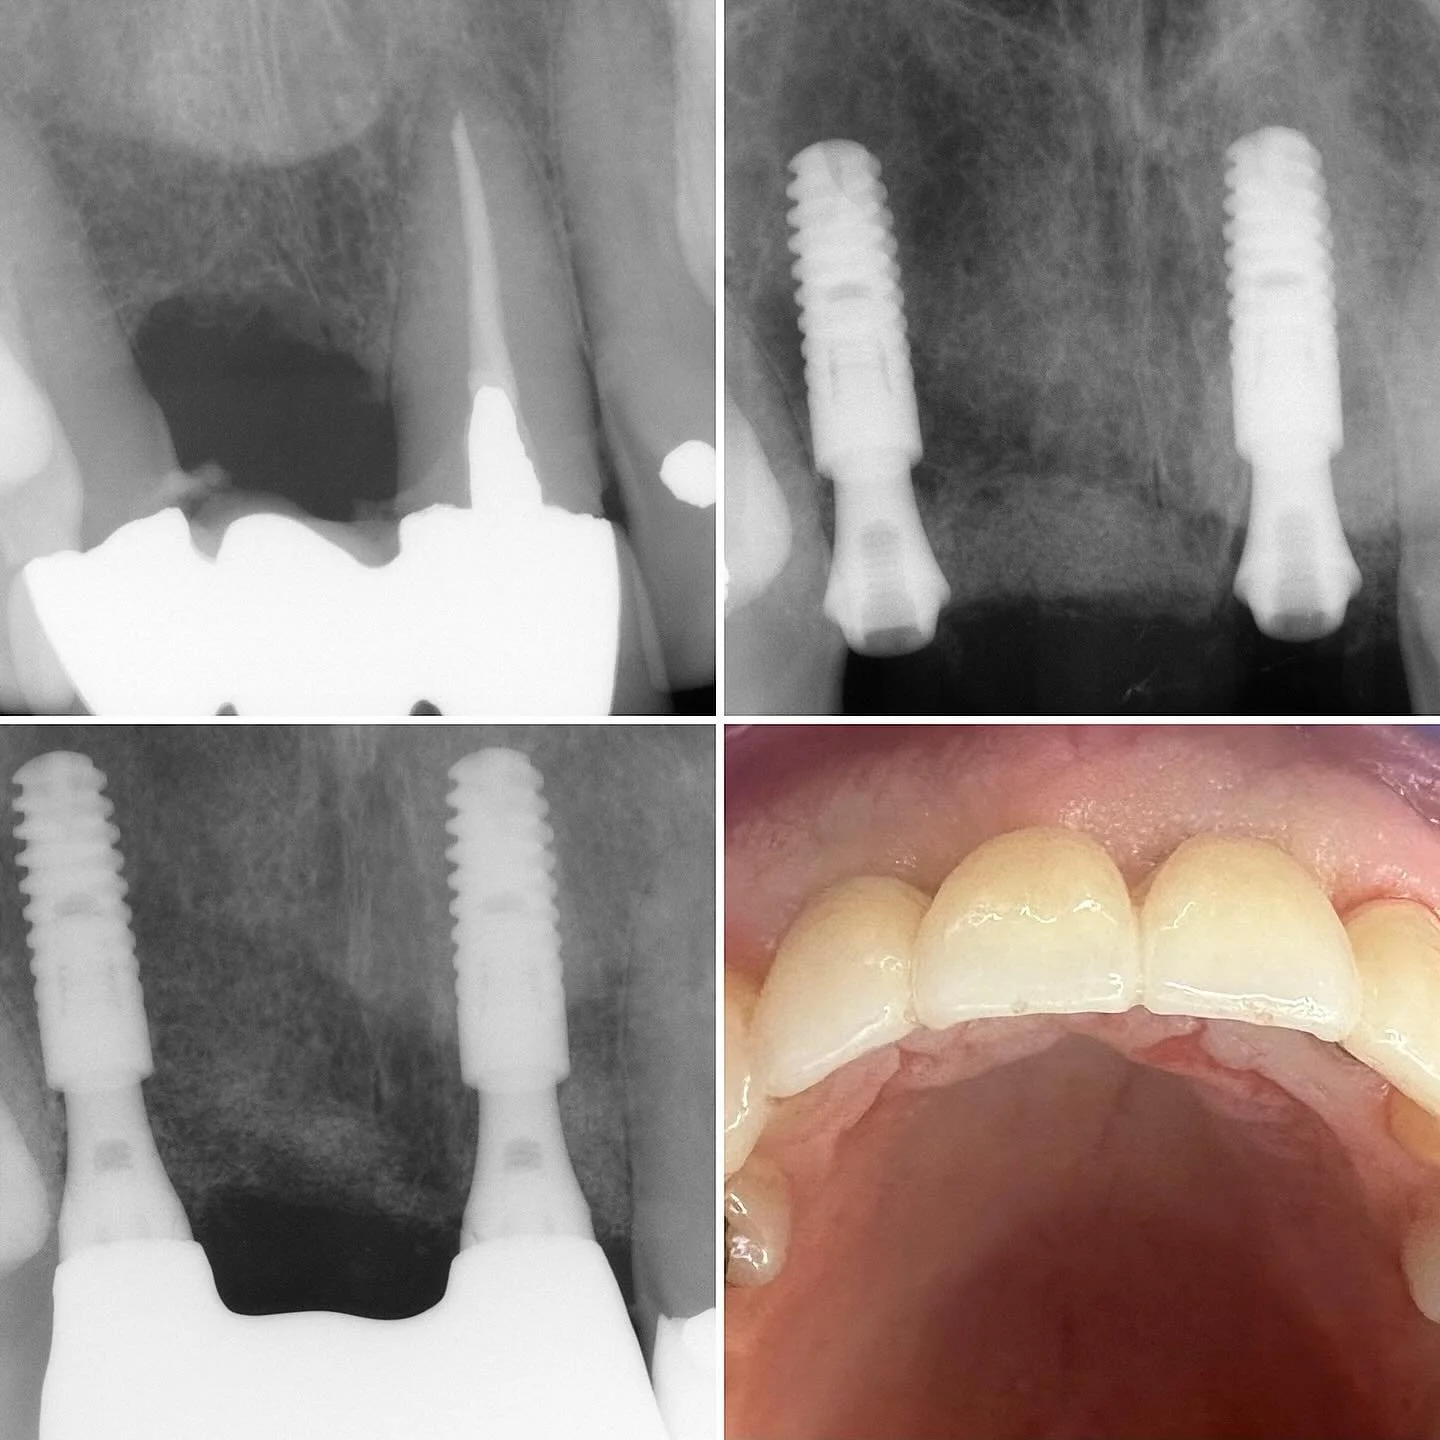

We are an award winning, local family run practice providing advanced implant, cosmetic and family dentistry

We donβt treat teeth, we treat people - you are unique, with individual needs and we have the solutions.